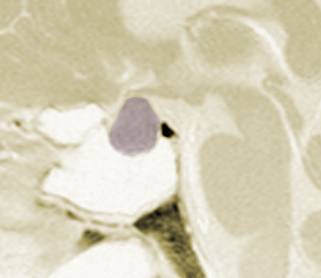

pituitary_bmc_sh.jpg (8160 bytes)

Data support a more definite role is in salvage therapy of recurrent tumors, and in particularly those in previously irradiated patients with low-lying disease in the cavernous sinus.

Whilst a marginal dose of 1500 cGy might be the target prescription, previous radiation dose received and proximity to the optic chiasm may argue for a lower dose prescription in individual cases. London, Mayo, Northwest, Johns Hopkins and see main site on pituitary tumors, see the reviews below other recent studies here and acromegaly here and here. A discussion of radiosurgery versus external beam is here.